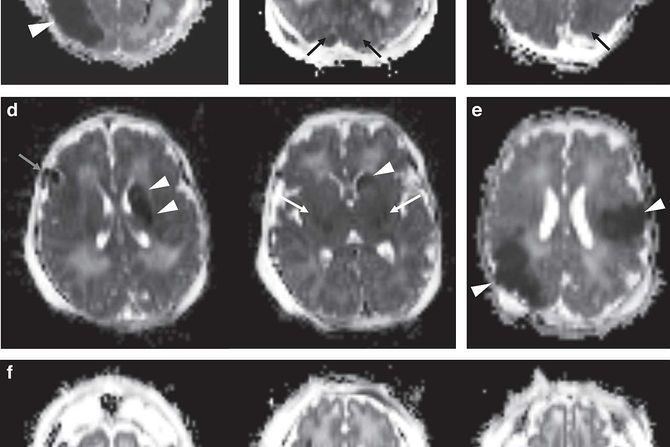

Otkriveno je da kod 4% novorođenčadi sa umerenim do teškim HIE snimanje magnetnom rezonancom ukazuje na PAIS.

Tri od četiri bebe koje su imale PAIS takođe su imale obrazac HIE oštećenja mozga i doživljavale teže komplikacije nego one bez PAIS.

Rezultati pokazuju vrednost studija velikog obima radi poboljšanja intervencija za neonatalnu povredu mozga. Studija naglašava značaj snimanja mozga magnetnom rezonancom u identifikaciji svih uzroka oštećenja mozga novorođenčadi podvrgnutoj terapeutskoj hipotermiji zbog HIE.